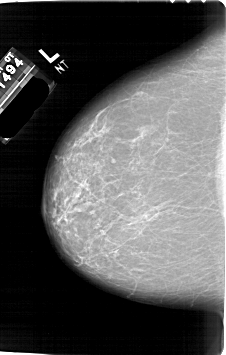

A_1751_1.LEFT_CC

LEFT_CC LINES 6736 PIXELS_PER_LINE 4291 BITS_PER_PIXEL 12 RESOLUTION 43.5 NON_OVERLAY